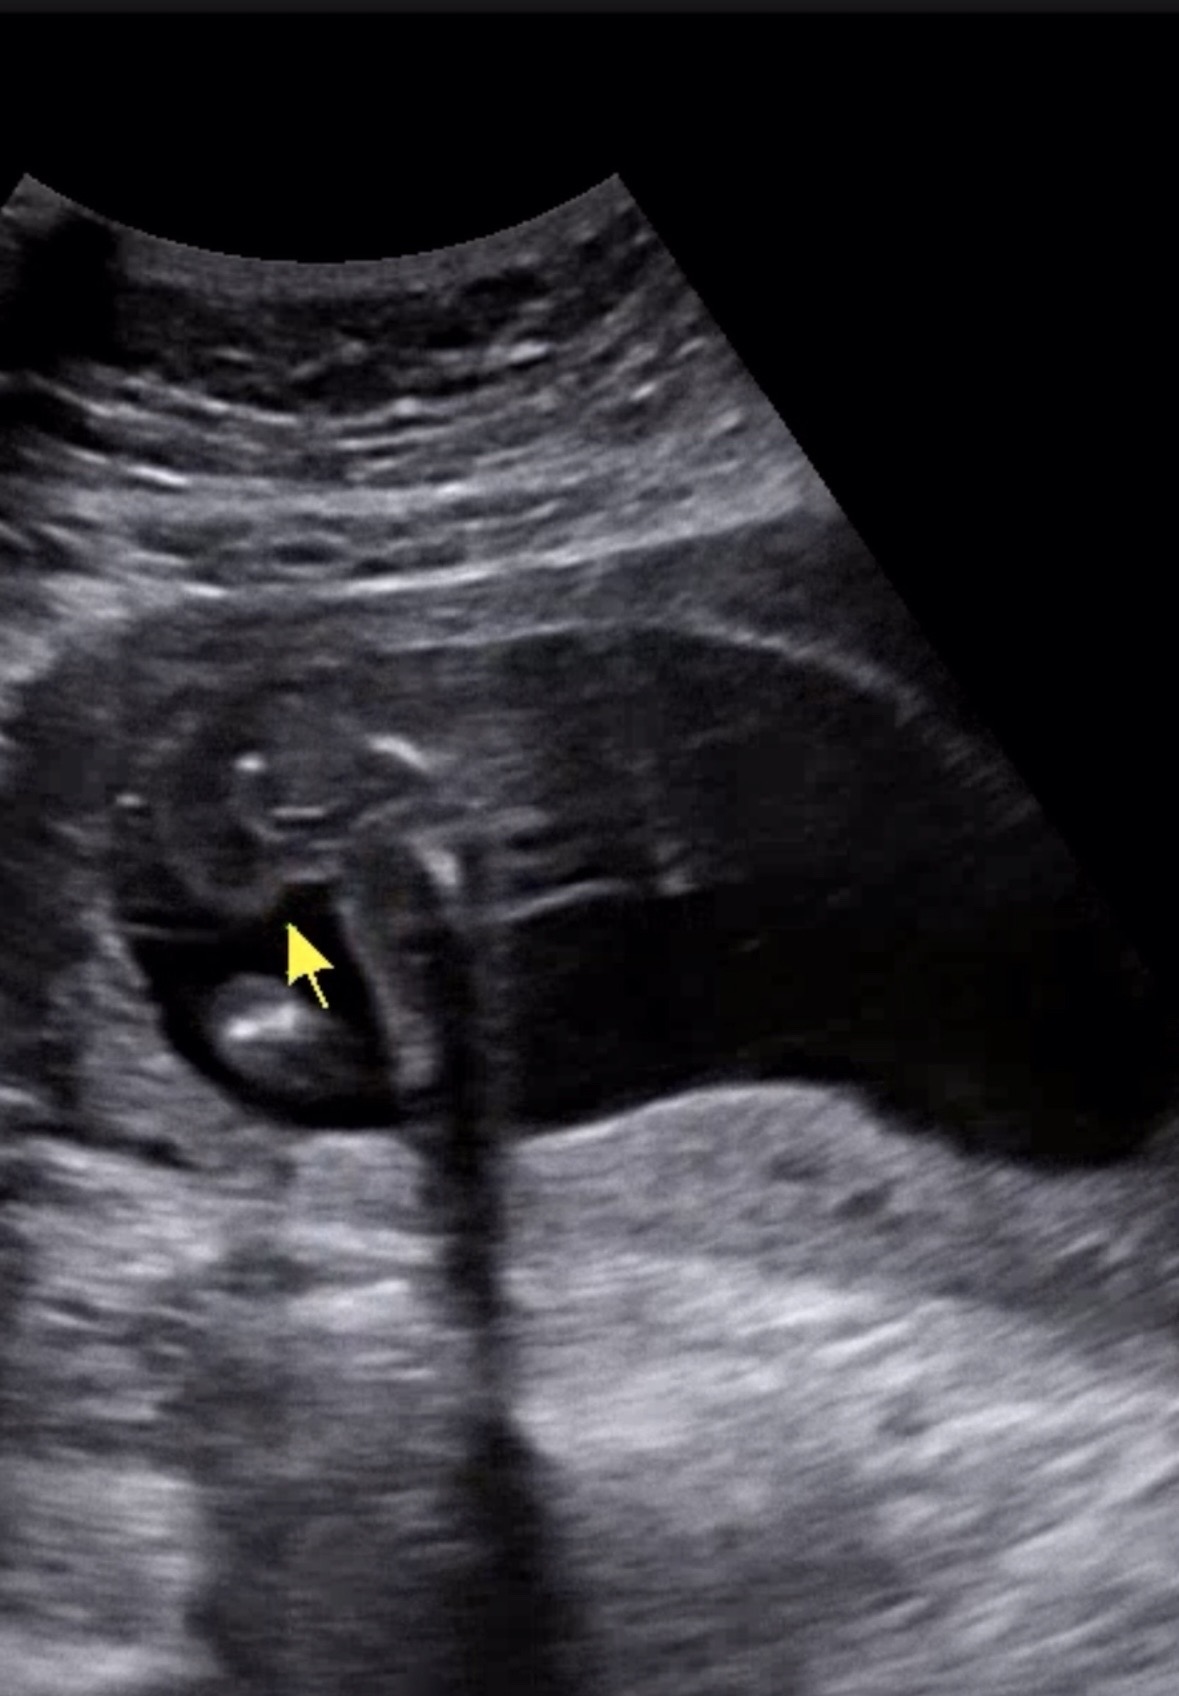

15주때 초음파룰 확인하고 아들을 원했지만 딸이라는 결과를 들었어요! 밑에서 봐도 옆에서 봐도 튀어나온 것은 없다고 해서 딸로 생각하고 젠더리빌까지 다했는데.. 오늘 두통이 너무 심해서 17주차에 병원을 또 갔고 15주 때 성별을 알려주신 선생님이 아닌 다른 선생님이였어요~ 아직도 딸인가요~? 했더니 저 사진에 화살표를 가르키며 사타구니사이가 애매하다고 아들일 수도 있겠네요~ 하시는거에요 ㅎㅎ…. 17주에 아들이라면 다리사이에 명확하게 보여야하는게 아닌가요..? 지금 너무너무 혼란스럽고 궁금한건 못참는 성격인데 토요일에 서브병원을 한번 더 갈지.. 아들로 바뀐건지 여러분들도 이런 경험이 있으셨는지 의견이 궁금합니다!!